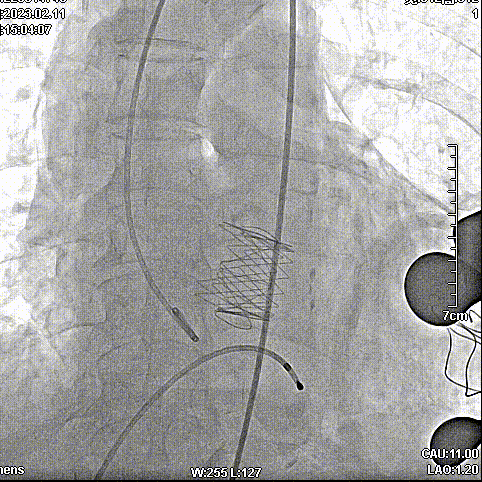

手术步骤